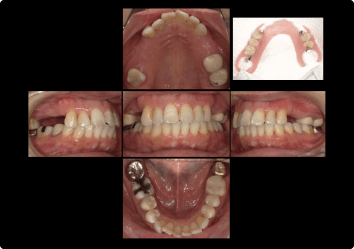

部分入れ歯が噛めない、違和感が強かった方のインプラント治療

BEFORE

AFTER

症例概要

年代・性別

50歳代 女性

主訴

入れ歯が噛めない

治療内容

上顎4番・6番インプラント、上5番 セラミッククラウン(デジタル)

治療期間

3ヶ月

治療のリスク

インプラント周囲炎のリスクがあるため、メンテナンスに来ていただきます。

治療費用

924,000円(税込)